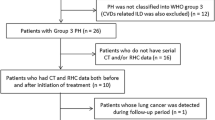

Clinical CT examinations covering the entire thorax were acquired from the electronic medical record. CT scans with a section thickness of 1–3 mm were used. It was independent of this study whether the CT was performed with contrast fluid or without. Image analysis was performed in collaboration with the Applied Chest Imaging Laboratory at Brigham and Women’s Hospital, Harvard Medical School, utilizing automated software based on the Chest Imaging Platform (www.chestimagingplatform.org) as previously described [4]. Lung field masks were extracted using a region-growing approach [12]. The pulmonary vasculature was extracted using a validated scale-space particle approach [13, 14] and the vessel scale was used to determine the vessel caliber [4]. After the automated CT analysis, the processing pipeline was manually verified. This included verification of lung masks to fit within the CT lung region and exclusion of CT scans with artifacts (Fig. 1). After the automated CT analysis, the vascular extraction was visually verified (Fig. 1). The following were calculated; the volume of vessels of varying sizes, measured as cross-sectional area, (Fig. 1); the total pulmonary vessel volume (TPVV), the subsegmental vessel volume, and the segmental vessel volume. The TPVV was measured to include both vessel walls and luminal blood. The TPVV included the combined intraparenchymal pulmonary vessels, while the blood volume in the subsegmental vessel was defined as vessels with nominal sizes below 10 mm2 in cross-sectional area (CSA) (BV < 10) and the segmental vessel in vessels within a nominal size of 20 to 90 mm2 in cross-sectional area (BV20-90).

An example of vascular reconstruction quality check outputs

A) depicts the output from the partial quality check. This step is used to make sure that the region of interest only includes the lung, and other organs i.e., the heart

B) depicts the output from the total vascular reconstruction. The quality check is used to make sure that larger regions of the pulmonary vasculature are not missing